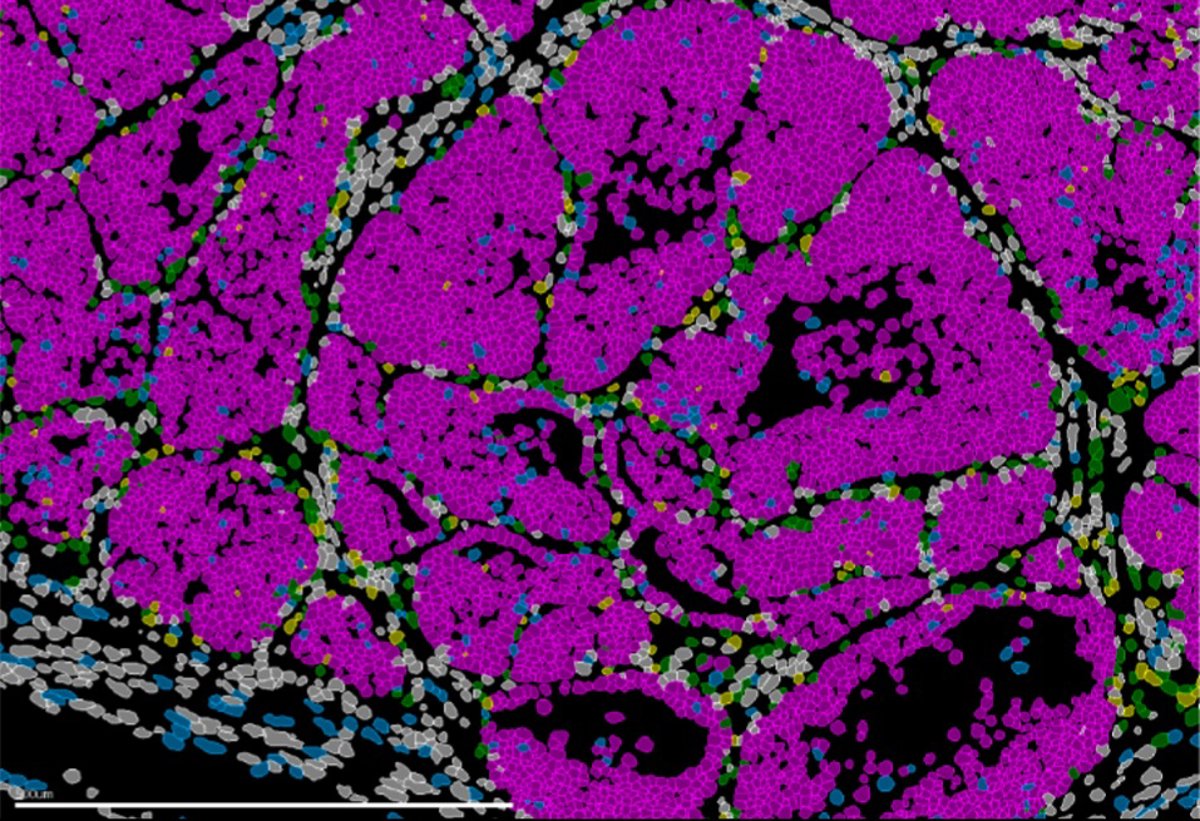

Imagen de un tumor de mama en ratón que muestra las distintas poblaciones celulares (células cancerosas en rosa). Tecnologías avanzadas de biología espacial permiten la identificación simultánea de todos los tipos celulares presentes en el tejido.

Imagen de un tumor de mama en ratón que muestra las distintas poblaciones celulares (células cancerosas en rosa). Tecnologías avanzadas de biología espacial permiten la identificación simultánea de todos los tipos celulares presentes en el tejido. - IN CSIC-UMH

En esas condiciones, las células combinan invasión y división celular, lo que las convierte "en las más peligrosas desde el punto de vista clínico". Para llegar a estas conclusiones, el equipo combinó modelos genéticos en ratón, análisis de célula única, estudios de cromatina y técnicas de transcriptómica espacial que permiten observar la organización y el comportamiento de las células directamente en el tejido tumoral.